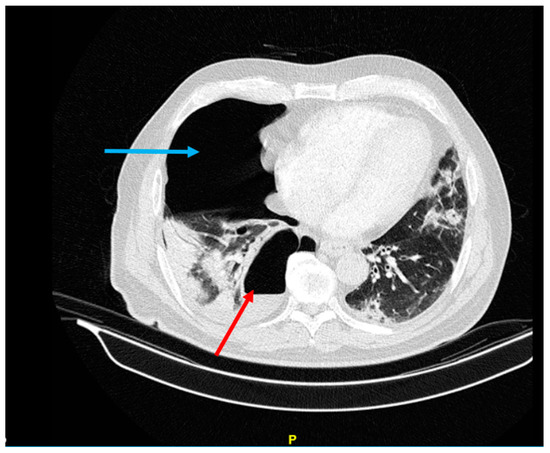

After eight days of hospitalization, the patient showed a relative improvement in his general condition and oxygenation and was discharged with the recommendation to take supplemental oxygen at home. The patient reported an SpO2 of 84–85% without supplemental oxygen and of 93% with oxygen at home. However, one week later, he developed pain in the right side of his chest, cough, and hemoptysis and was admitted to the Valiasr Hospital in Zanjan, Iran. Upon admission, the patient was conscious and oriented, with SpO2 85%, blood pressure 120/80 mmHg, heart rate 90/min, respiratory rate 18/min, and body temperature 38 °C. During the physical examination, a decrease in respiratory sounds on the right lung and fine crackles in the left lung were observed. A CT scan revealed a right pneumothorax with multiple calcified nodules in the parenchyma of both lungs, several cavities in the lower lobe of the right lung with air-fluid level and more cavities adjacent to the spine, ground-glass opacities (GGO), and multiple bilateral consolidations in favor of COVID-19 (Figure 5).

Figure 5.

Right lung pneumothorax (blue arrow) and right lung abscess containing air-fluid level in the RLL (red arrow).

In the BAL sample, Klebsiella pneumoniae grew with a colony count of >105, which was classified as multi-drug-resistant (MDR). The patient was prescribed colistin 3Mu IV TDS and clindamycin 600 mg/TDS as recommended by the infectious disease specialist. The BAL sample was negative for fungus and BK. After 5 days, the chest tube was removed due to the expanding lung and improved pneumothorax, but the antibiotic therapy continued (Figure 6).

Figure 6.

CT scan of patient 5 days after pneumothorax and removal the chest tube. The lack of abscess shrinkage is noticeable (red arrow).